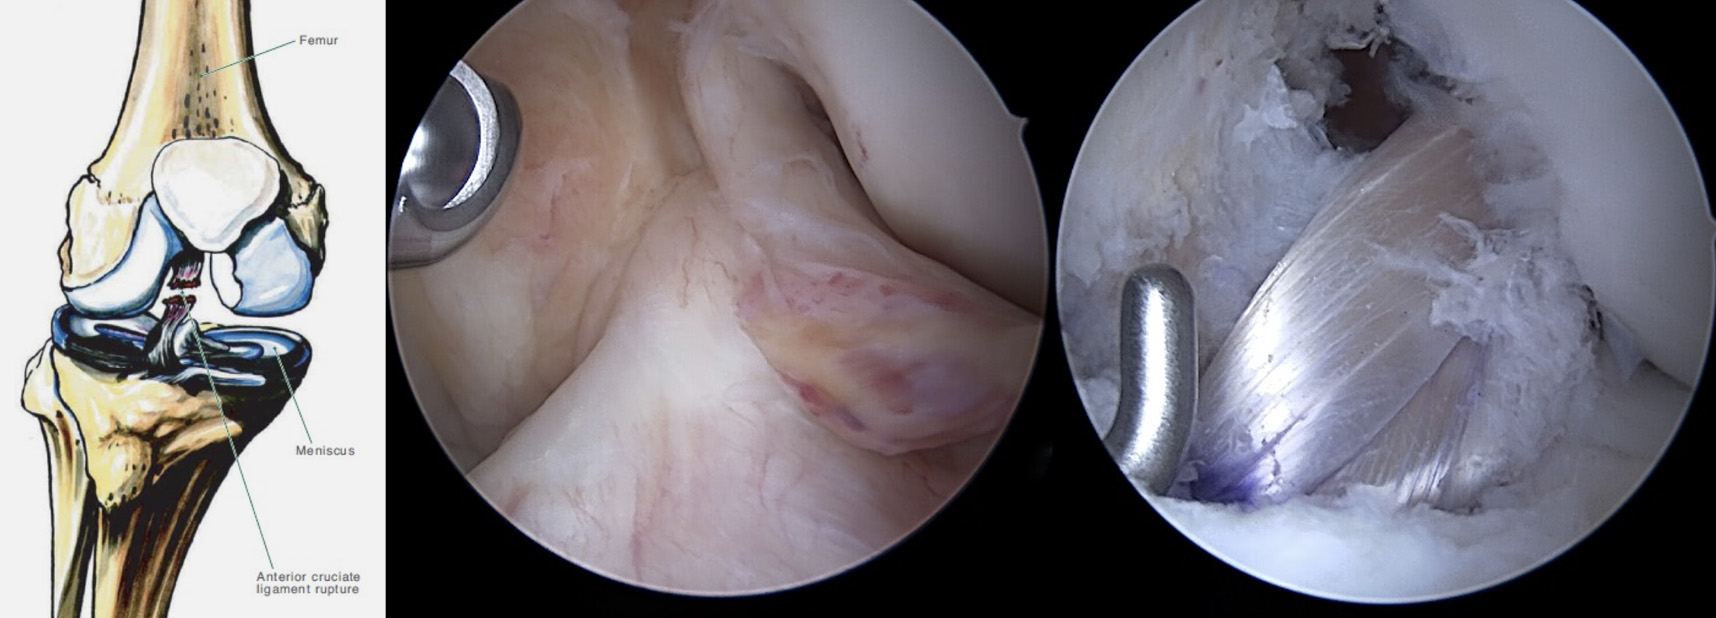

No momento da lesão (figura 4), o paciente refere habitualmente a sensação de “pop” dentro da articulação. Pode igualmente ter a perceção de perda de congruência articular “joelho saiu do sítio”. Esta apresentação é acompanhada de dor, derrame articular de instalação rápida (até 2 horas) e pode impedir a realização de carga.

LCA intacto; rotura do LCA

Figura 4 – Imagem da esquerda evidencia LCA intacto; Imagem da direita, rotura do LCA